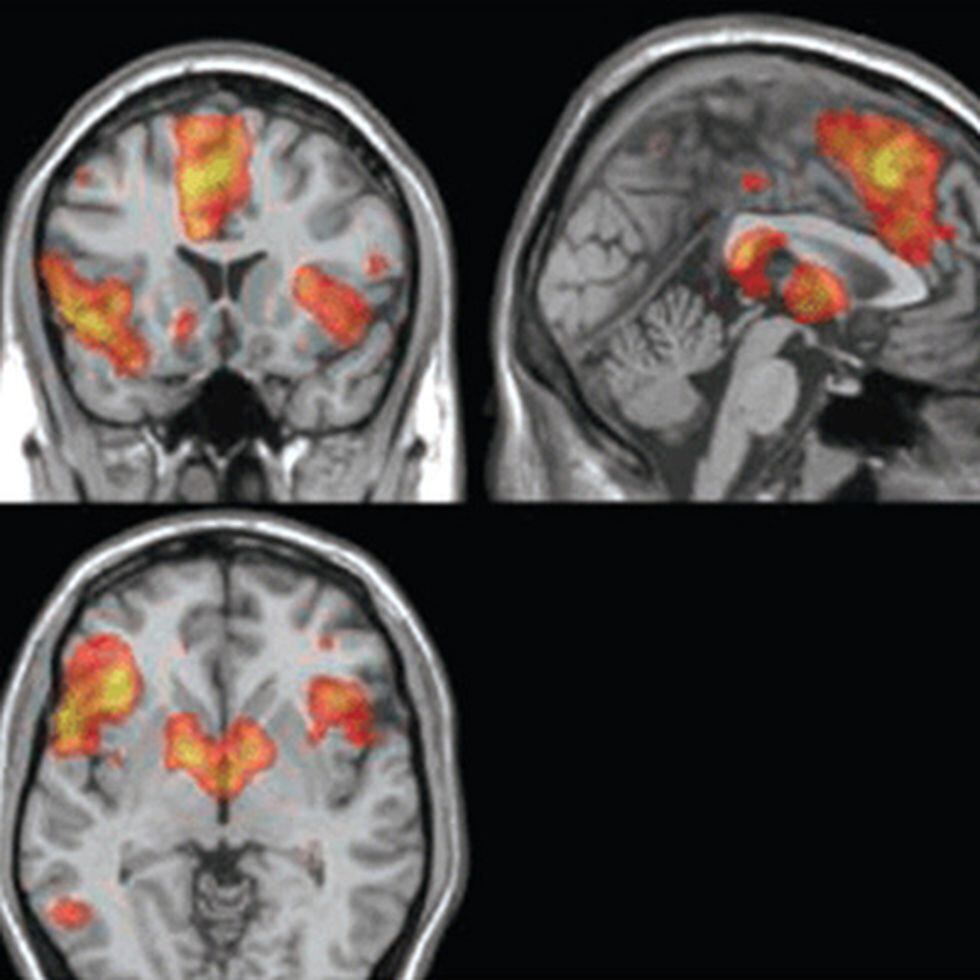

Engineer Team : RESONANCIA MAGNETICA Magnetic Resonance Imaging – Clinical Images Hallazgos por resonancia magnética cerebral de nuestro paciente. M, 21 … Imágenes por resonancia magnética anormales como predictoras de mal … Imágenes por resonancia magnética anormales como predictoras de mal … Lesiones en resonancia magnética (RM) del encéfalo y la médula espinal … Pin en Resonancia Magnética del Encéfalo A) Resonancia magnética cerebral (RMC) mostrando infartos en … Caso 1: Edema cerebral visualizado mediante RM. (A) Secuencia T1 plano … Rascacielos dormir pasta tac y resonancia diferencias retrasar … Pin on Apuntes de Enfermería y T.C.A.E Resonancia magnética cerebral secuencia T2, que muestra lesión … Meningitis aguda en la enfermedad de Behçet | Reumatología Clínica Resonancia magnética coronal normal del cerebro Fotografía de stock – Alamy Imágenes de resonancia magnética, la imagen de la cabeza en diferentes … Resonancia magnética cerebral A) protocolo T1 sagital (Caso 1). Se … Resonancia magnética cerebral. Secuencia T1 corte sagital. Atrofia … Resonancia magnética de cerebro, cortes axiales, secuencias T2. Señal … Resonancia magnética de cráneo. A y B) Cortes axiales FLAIR … Resonancia magnética (RM) de cerebro, corte axial ponderado en T2: la … RM cerebral: Interpretación paso a paso | Kenhub Resonancia magnética de cerebro, cortes axiales, secuencias T2. Señal … De Resonancia Magnética De Cerebro Foto de archivo – Imagen de arteria … Top 107+ Imagenes de resonancia cerebral normal – Destinomexico.mx -Imagen por resonancia magnética del cerebro. a) Cortes sagital y axial … resonanCia magnétiCa Cerebral donde se observa hiperintensidad a nivel … MRI (Imagen de resonancia magnética) – Tomografía computarizada de la … Meningioma – NCI Imágenes por resonancia magnética coloreadas del cerebro sano del … Resonancia magnética cerebral en secuencia FLAIR, que muestra lesiones … Contraste resonancia magnetica cerebral – senturinthegreen Relación de los espacios de Virchow-Robin con la enfermedad de … Gliomatosis cerebral – Instituto Nacional del Cáncer Pin en Neurology. Recomendaciones para la utilización e interpretación de los estudios de … Fotografía De La Proyección De Imagen De Resonancia Magnética Del … atmósfera Dirigir Cumplir anatomia resonancia magnetica Desarrollar … Pin en #MEDICINA,#SALUD Resonancia magnética de la nasofaringe De Resonancia Magnética De Cerebro Foto de archivo – Imagen de polilla … Atrofia cortical global de predominio parietal en la Resonancia … Resonancia magnética cerebral | Download Scientific Diagram Neuroblog: Resonancia magnética cerebral en la trombosis crónica de … De Resonancia Magnética De Cerebro Imagen de archivo – Imagen de … ¿Cuáles son los riesgos de la resonancia magnética? – Integra Salud … Resonancia magnética cerebral al decimocuarto día de ingreso: área … Resonancia magnética. Corte axial mostrando área infartada en el … Resonancia magnética cerebral del paciente AV evidenciando lesiones en … -Ressonância magnética de encéfalo mostrando múltiplas imagens … Resonancia magnética cerebral secuencia FLAIR (Fluid Attenuated … Resonancia magnética cerebral con protocolo de epilepsia, en sección … Resonancia magnética cerebral en corte sagital. Se observa una evidente … Resonancia magnética craneal en la que se evidencian lesiones … Logran visualizar el cerebro a detalle más completo tras una resonancia … Así decide el cerebro la severidad de un castigo De Resonancia Magnética De Cerebro, Imagen de archivo – Imagen de … A) Resonancia magnética cerebral; Secuencia Tof: oclusión de arteria … Un estudio asocia la ansiedad con la aparición rápida del Alzheimer IMÁGENES DE 18 F-PR04.MZ PET FUSIONADA CON RESONANCIA MAGNÉTICA … Imágenes por resonancia magnética anormales como predictoras de mal … Tumores de la región pineal – Instituto Nacional del Cáncer Epilepsia: una historia de voces y fantasmas | Neurología Contribución de las imágenes de resonancia magnética por tensor de … Resonancia magnética secuencia T2 plano coronal de quiste epidermoide … Resonancia Magnética Cerebral del paciente: a. Aumento de… | Download … Resonancia magnética cerebral 2022 Síndrome de hemiconvulsión-hemiplejía-epilepsia. Seguimiento de un caso … Enfoque Radiologico: La resonancia magnética permite detectar lesiones … Resonancia magnética craneal T1 con contraste que muestra angiomatosis … guidewiz – Blog Resonancia magnética cerebral, secuencia SWI. Ribete hipointenso en la … resonAnCiA mAgnétiCA de ColumnA Con gAdolinio. Corte sAgitAl en t1 de … SEMANA 12: FUNDAMENTOS DE RESONANCIA MAGNÉTICA NUCLEAR. INDICACIONES Y … DIAGNÓSTICO DE ESCLEROSIS MÚLTIP Magnetic resonance imaging of the brain – Alchetron, the free social … Resonancia magnética de órbitas | Instituto Radiológico Dr. E Castillo Alteración de la marcha en un paciente post-trasplante hepático Resonancia magnética cerebral de un paciente sano (Ay B) y paciente que … Utilidad de la resonancia magnética craneal para el diagnóstico de la … Resonancia Magnética Del Cerebro El Tumor Cerebral Foto de stock y más … De Resonancia Magnética De Cerebro Imagen de archivo – Imagen de … ABDALLA RADIOLOGIA: NEURINOMA ACUSTICO Atrofia cortical global de predominio parietal en la Resonancia … Resonancia Magnética : Producción de la imagen MRI Brain Scan — Stock Photo © Bunyos30 #18724051 Mri (imagen de resonancia magnética) Monitor con imagen de captura de … Tomografía computarizada vs resonancia magnética: diferencia y … Tumores Cerebrales – Unidad de Neurocirugía RGS Resonancia magnética de la columna, sección sagital. Observe los discos … La resonancia magnética, una técnica imprescindible en el diagnóstico … Perfusión Cerebral por Resonancia Magnética | ¿Qué es? ¿Necesita Contraste? Resonancia Magnética Cerebro A: resonancia magnética, T2 coronal preoperatoria; se observa lesión en … Resonancia magnética cerebral — Foto de stock © Bunyos30 #27340623 La resonancia magnética se perfila como detector de mentiras | Futuro … Resonancia magnética cerebral en T1 con gadolinio, cortes axial (a … MRI brain : show brain tumor at right parietal lobe of cerebrum — Stock … NEUROIMÁGENES EN ENFERMEDAD DE PARKINSON: ROL DE LA RESONANCIA …